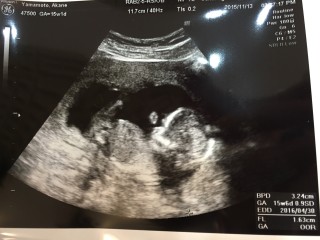

体外受精でやっと来てくれた子です。お腹ぽんぽこりんで可愛い…別アングルで男の子と判明しました!いつもこっち向いててくれてありがとう!笑 CRL9.17でした。胎動はまださっぱりですー

3週間ぶりの健診でした。 赤ちゃんはまた成長してて心拍もしっかり聞こえてとても元気でした。 はじめてのおなかの上からのエコーだったんだけど見づらい... 私も主人もしつこいくらい性別きになってて(笑)試しに聞いてみたらおそらく男の子だろうとのこと。 つぎは4週間後、 次回でわかるといいな